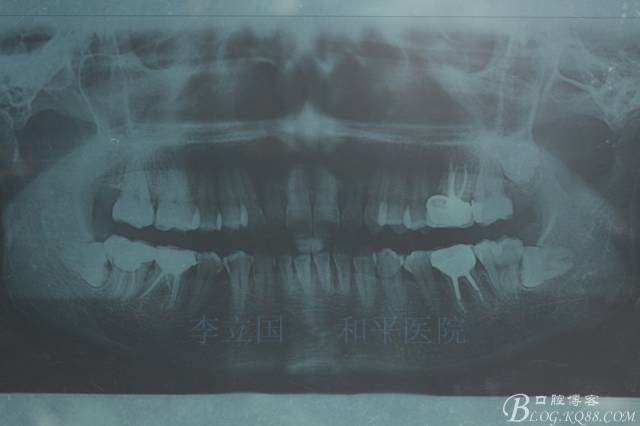

1.拔除14、24、31。

2.磨牙關(guān)系一側(cè)完全遠(yuǎn)中,一側(cè)遠(yuǎn)中尖対尖,采用兩個上4,一個下1的拔牙模式。

3.上頜應(yīng)用支抗釘。表麻下在56牙槽間隔植入,注意因使用的為鈦合金釘,一直保持植入角度與骨面成60度角,不要垂直植入再改變角度。要求即刻加載,即刻加載力值2盎司。